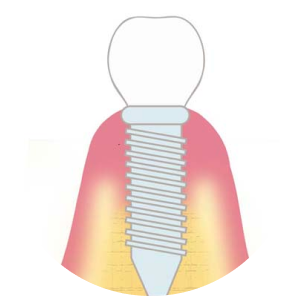

代表的な再生療法のひとつが「GBR(骨誘導再生法)」です。骨が不足した部位に自家骨や人工骨を補填し、特殊な膜(メンブレン)で覆うことで、骨の再生を促しインプラントの土台を築く方法です。

また、上顎奥歯など骨が特に薄い部位には「サイナスリフト(上顎洞底挙上術)」が適応されます。上顎洞と呼ばれる空洞の底を持ち上げ、その下に骨を造成することで、十分なインプラント埋入スペースを確保することが可能になります。

これらの高度な再生治療は、歯科用CTや精密シミュレーション技術、そして確かな経験を持つ術者による対応が前提となります。